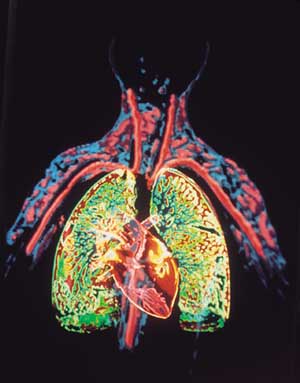

القلب Heart عضو عضلي يضخ الدم في جسم الإنسان. ومع كل دقّة يدفع القلب الدم الضروري للحياة عبر جسم الإنسان. ويحمل الدم الأكسجين والغذاء لكل خلايا الجسم وتبدأ دقات القلب ذات الإيقاع المنتظم قبل سبعة أشهر من ميلاد الطفل تقريبًا. وعندما يتوقف القلب تتوقف الحياة، إلا إذا ساعدت أجهزة آلية خاصة على دوران وأكسجة الدم. والقلب عضو عضلي مجوّف كبير، ينقسم إلى مضختين متجاورتين. وتنقل الأوردة الدموية الدم في جميع أنحاء الجسم إلى المضخة الواقعة في الجهة اليمنى التي ترسله بدورها إلى الرئتين لحمل الأكسجين، ومن ثم، ينساب الدم المؤكسد إلى الجهة اليسرى من القلب التي تضخه إلى أجزاء الجسم المختلفة بوساطة الشرايين. وهناك صمامات تتحكم في سريان الدم داخل القلب. والمضخة اليسرى، التي تدفع الدم إلى جميع أنحاء الجسم أقوى وأكبر حجمًا من المضخة اليمنى. والقلب والتشكيلات الأنبوبية الأخرى مثل الشرايين والأوردة والشعيرات تسمى جميعًا الجهاز الدوري أو الجهاز القلبي الوعائي. ينظم الجهاز العصبي عمل القلب وأجزاء أخرى من الجهاز الدوري. وينظم الجهاز العصبي التلقائي، وهو جزء من الجهاز العصبي، ضربات القلب (النبض)، فيقللها أو يزيدها حسب حاجة الجسم؛ لذلك فإن القلب يدق بصورة هادئة مثلاً عندما يكون الإنسان نائمًا ويزود الجسم بكمية قليلة نسبياً من الأكسجين. وقد تزداد سرعة ضربات القلب مرة أخرى لتزيد كمية مردود الأكسجين للجسم بغزارة. ويحدث هذا عندما يزاول الإنسان التمارين الرياضية أو عندما يصاب بالخوف أو عندما يحتاج للمقاومة أو العراك أو الجري. وقد يصيب المرض أو الخلل أي جزء من أجزاء القلب أو الأوعية الدموية، ويعتبر ذلك من الأسباب الرئيسية للوفاة في البلدان الصناعية. وأكثر أمراض القلب شيوعًا هي التي تصيب الشرايين التي تغذي القلب نفسه بالدم. والخلل الذي يصيب هذه الشرايين قد يتطور مع سنوات عمر الإنسان. فترسُّب المواد الدهنية مثلاً، يؤدي إلى انسداد شرياني وإلى قلة كمية الدم التي تزود القلب. وإذا استقبلت عضلة القلب كمية قليلة من الدم فإن هذا قد يؤثر في أدائها أو إلى موتها. ويسمى هذا الخلل أو التلف الناتج من قلة إمداد عضلة القلب بالدم النوبة القلبية. والنوبة القلبية الخفيفة قد تجبر الإنسان لكي يعيش حياة أقل نشاطًا وحركة. أما النوبة القلبية القاسية أو العنيفة فتجعل القلب غير قادر على إمداد الجسم بكمية كافية من الدم، حتى في حالة الراحة الكاملة، وقد تؤدي إلى الوفاة. وقد تصيب الأمراض أجزاء أُخرى من القلب وقد يؤدي هذا إلى تأثير مدمّر مشابه. تحققت أهم التطورات الطبية الحديثة في مجال طب القلب، وهو حقل طبي يعنى بالأمراض التي تصيب القلب والأوعية الدموية. ومنذ آلاف السنين، لم يكن مرضى القلب يعرفون أصلاً أن لهم هذه المشكلة. وفي التسعينيات من القرن العشرين الميلادي، تعلم الأطباء كيف يشخصون ويعالجون بعض حالات مرض القلب التي كان علاجها علاجها مستحيلاً في السابق، وكانت تعني الوفاة لمن يصاب بها. وأدّى اكتشاف الأدوية والتطور الهائل في الجراحة إلى إعطاء عدد من مرضى القلب أملاً في الحياة، وبدأ الأطباء بزراعة القلوب بل طوّروا أجهزة تقوم بعمل القلب مؤقتًا. واليوم تُجرى كثير من الأبحاث في علم القلب ووظائفه، ويتم التركيز على دراسة الأسباب التي تؤدي إلى أمراض القلب حتى يمكن تفاديها. وتدرس أبحاث أخرى إمكانية خفض حالات الموت والعجز التي تنتج من أمراض القلب، عن طريق دعم وتطوير أدوية وعقاقير معالجة جديدة واستحداث قلب صناعي فعّال. هذه المقالة عن قلب الإنسان بصورة خاصة، والجزء الأخير منها يصف قلب الحشرات والسمك والطيور والحيوانات الأخرى. ولمزيد من المعلومات عن عمل الدم في الجسم،

تشكل العضلة القلبية النسيج الفعال وظيفيا من القلب حيث يؤمن تقلصها انتقال الدم وضخه من القلب إلى باقي الأعضاء مما يجعل القلب محطة الضخ الرئيسية للدم من القلب إلى العضاء لتزويدها بالأكسجين المحمل في الدم القادم من الرئتين, من ثم يقوم القلب بضخ الدم القادم من العضاء والمحمل بثاني أكسيد الكربون إلى الرئتين لتنقيته و تحميله من جديد بالأكسجين.

تنظم حركة الدم في القلب صمامات (تدعى أيضا دسامات) تشكل بوابات وحيدة الإتجاهات تؤمن انتقال الدم من الأذينة إلى البطين ولا تسمح بالانتقال العكسي, فالتجمع الأساسي للدم الوارد للقلب يحدث في الأذينة اليمنى لينتقل بعد ذلك إلى البطين الأيمن, يقوم البطين الأيمن بضخ الدم للرئتين, يعود الدم بعد تنقيته من الرئتين إلى الأذينة اليسرى, من الأذينة اليسرى ينتقل للبطين الأيسر الذي يضخه بدوره عبر الشريان الأبهر، أو الشريان الرئيسي، إلى باقي الأعضاء.